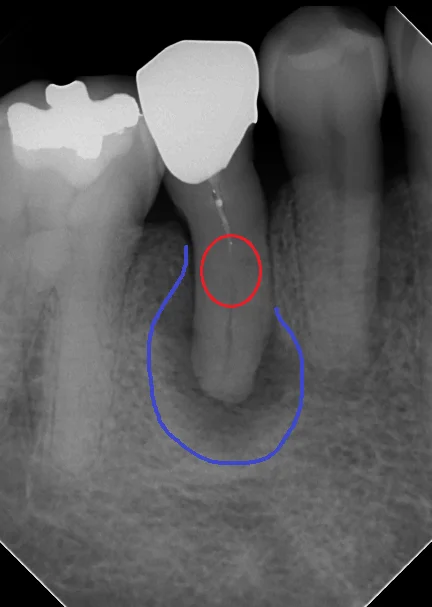

すこし分かりやすい様にマークを入れるとこういう感じです。

閉鎖根管の治療には根気が必要|坂寄歯科医院(取手市藤代) - 画像2

根管が閉塞しているのが、赤丸の部分です。そこの上の方には白い薬剤が軽く入っていますが、下の方には何も入っていないのが分かると思います。

画像上で青くしている所が膿が溜まっている箇所になります。

非常に広範囲に膿が溜まっていますね。